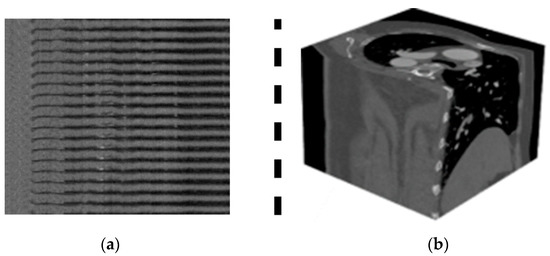

The 3D CCTA images of 1000 patients are deposited in dataset 2. The images were captured using a Siemens 128-slice dual-source scanner. The size of the images is 512 × 512 × (206–275) voxels. The images were collected from the Guangdong Provincial People’s hospital between April 2012 and December 2018. The average ages of females and males were 59.98 and 57.68 years, respectively. The dataset repository [6] is publicly available for the researchers. In addition, it offers an image segmentation method for extracting images of coronary arteries from raw 3D images. Figure 2a,b are the raw images of datasets 1 and 2, respectively. Table 1 presents the characteristics of the dataset.

Figure 2. (a) Dataset 1. (b) Dataset 2.